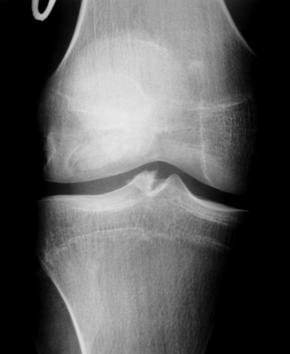

1.2.1. Radiografia standard

Radiografia standard are un rol limitat in evaluarea leziunilor cartilajului articular. Cu toate acestea, radiografia este o examinare de rutina in patologia genunchiului, care poate aduce informatii utile pentru diagnosticarea leziunilor condrale si a patologiei asociate cu acestea.

Radiografiile standard evidentiaza ingustarea spatiului articular, dezaxari, osteofitoza, scleroza subcondrala, chiste subcondrale, deformari ale suprafetelor articulare si ale articulatiei in artroza De asemenea, largirea spatiului articular (cresterea) a fost asociat cu scaderea simptomatologiei artrozice [11].

In osteocondrita disecanta se evidentiaza scleroza subcondrala si fragmentele osteocondrale detasate (fig. 1.3),

Fig. 1.3 Radiografii degenunchi incidente AP si LL - fragmente osteocondrale in osteocondrita disecanta a condilului femural extern, unul dintre ele migrat anterior a determinat blocajul genunchiului |